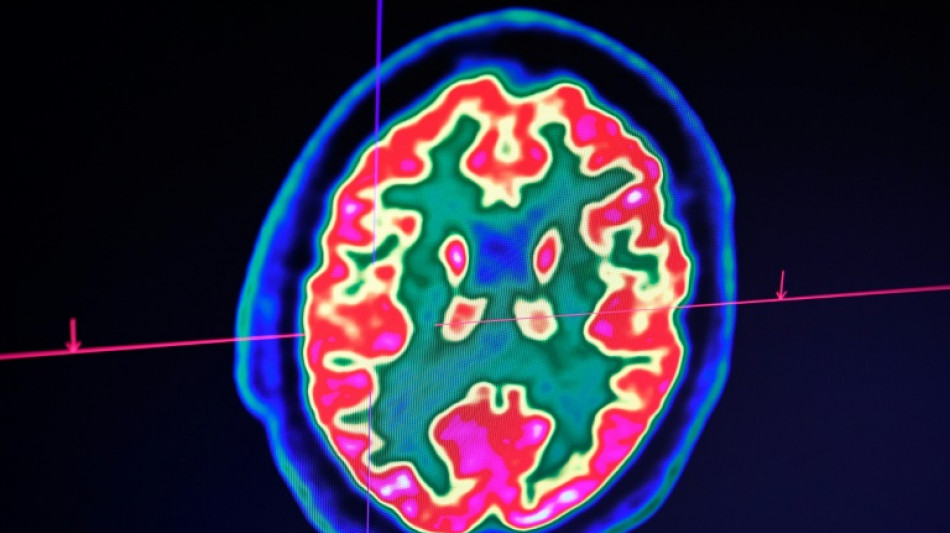

Sclérose en plaques: la découverte d'un lien avec un virus fait espérer une meilleure riposte

La découverte récente d'un lien entre la sclérose en plaques et le virus d'Epstein-Barr fait espérer une meilleure riposte à terme face à cette maladie, soulignent des spécialistes de la sclérose en plaques avant la journée mondiale de cette maladie, lundi.

Celle-ci est une maladie auto-immune du système nerveux central (cerveau et moelle épinière). Elle provoque un dérèglement du système immunitaire, qui s'attaque à la myéline, la gaine protectrice des fibres nerveuses.

On estime que plus de 2,8 millions de personnes sont touchées par cette maladie auto-immune dans le monde, dont environ 110.000 personnes en France. Les enfants et adolescents restent une minorité des cas, mais la maladie peut avoir démarré bien avant de pouvoir être diagnostiquée.